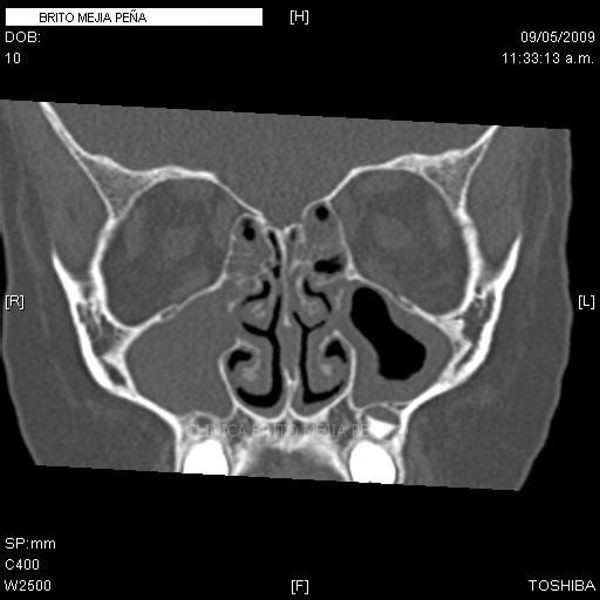

Envíado por BMP Imágenes Diagnósticas

BMP Imágenes Diagnósticas